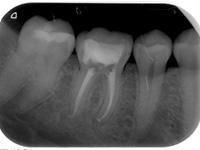

traitements endodontiques

Une carie profonde exige souvent un traitement endodontique avant la restauration de la dent, car les bactéries et leurs toxines se sont développées dans les racines.